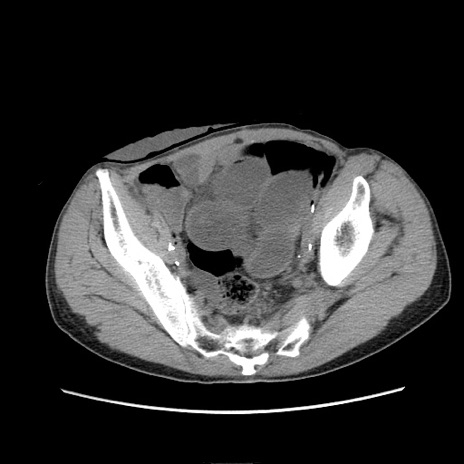

症例11(横断像)

【症例】 60歳代男性

【主訴】 下腹部痛

【現病歴】 本日夜中より下腹部痛の症状認め、受診。

【既往歴】 膀胱癌(膀胱全摘+尿管皮膚瘻術) 、胃癌術後

【身体所見】 BT 35.3℃、PR 58/min、BP 136/98mHg、腹部平坦、軟、腸蠕動音±、ストマ留置あり、左上腹部~正中部に圧痛あり、反跳痛なし。

【データ】WBC 5100、CRP0.01